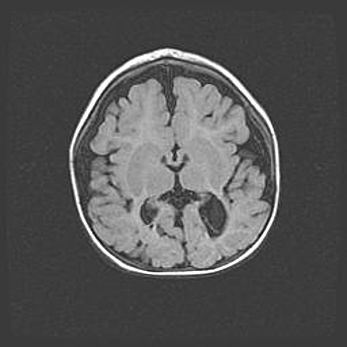

Лейкомаляция с кистозно-глиозной дегенерацией головного мозга.

Возраст: 2 месяца 25 дней

Вес: 6400 г

Окружность головы: 40 см

Срок гестации: 41 неделя

Лейкомаляцию относят к ишемически-гипоксическим повреждениям головного мозга, диагностируемым у новорожденных. При лейкомаляции в головном мозге обнаруживают очаги некроза, возникшие после тяжелой гипоксии и нарушения кровотока. В процессе морфогенеза очаги проходят три стадии: 1) развития некроза, 2) резорбции и 3) формирования глиозного рубца или кисты. Перивентрикулярная лейкомаляция (ПЛ) встречается примерно в 12% случаев среди новорожденных, обычно – у недоношенных детей, причем, частота ее зависит от массы, с которой младенец появился на свет. Наибольшее число малышей страдает лейкомаляцией, если масса при рождении 1500-2500 г.